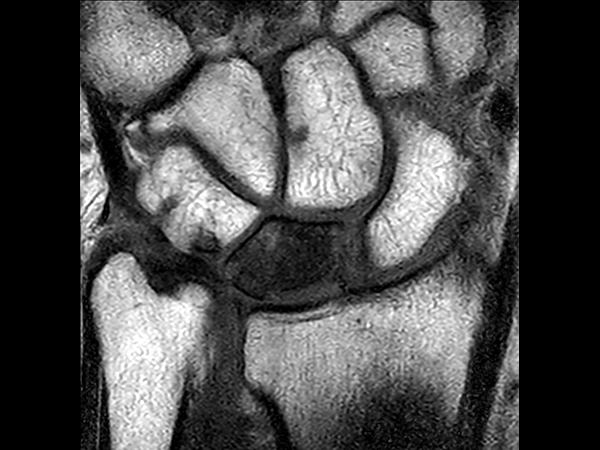

Patient with a lesion in his wrist. dS Microscopy coil set is used, consisting of two 47 mm coils, for small field-of-view imaging with high in-slice spatial resolution and a high signal-to-noise ratio. Compressed SENSE is used in all sequences to shorten the overall exam time for the patient.

Coronal T2w TSECompressed SENSE